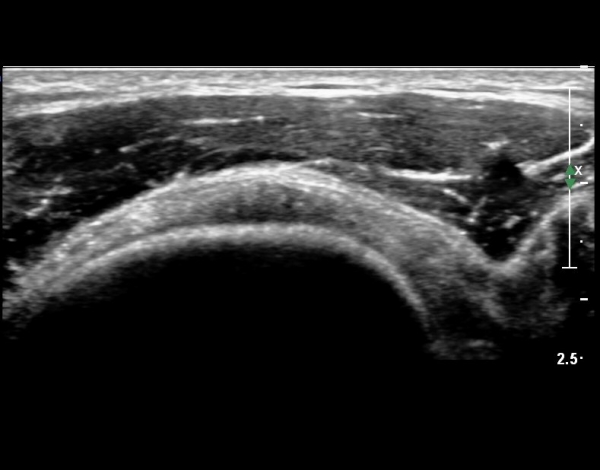

ÀÌµÎ¹Ú±Ù°Ç È¾´Ü¸é°Ë»ç¿¡¼­ °Ç ÁÖÀ§ ¼ö¾×Àú·ù µî ƯÀÌ ¼Ò°ßÀ» º¸ÀÌÁö ¾Ê¾Ò´Ù(»çÁø 1, 2)